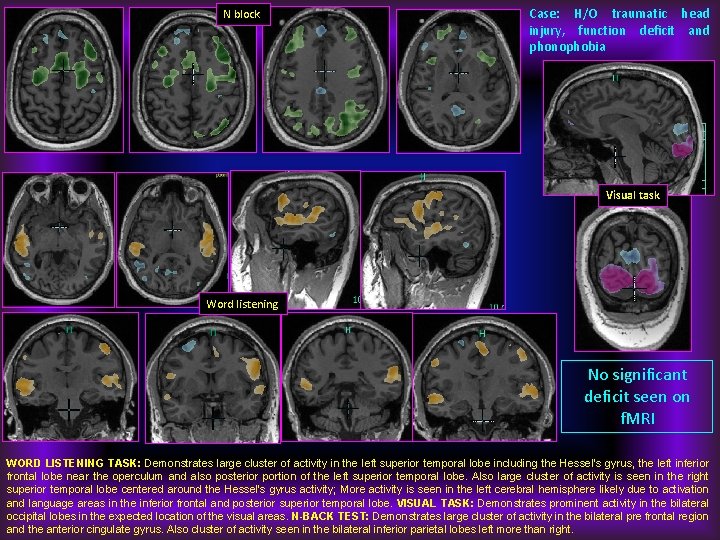

N block Case: H/O traumatic head injury, function deficit and phonophobia Visual task Word listening No significant deficit seen on f. MRI WORD LISTENING TASK: Demonstrates large cluster of activity in the left superior temporal lobe including the Hessel's gyrus, the left inferior frontal lobe near the operculum and also posterior portion of the left superior temporal lobe. Also large cluster of activity is seen in the right superior temporal lobe centered around the Hessel's gyrus activity; More activity is seen in the left cerebral hemisphere likely due to activation and language areas in the inferior frontal and posterior superior temporal lobe. VISUAL TASK: Demonstrates prominent activity in the bilateral occipital lobes in the expected location of the visual areas. N-BACK TEST: Demonstrates large cluster of activity in the bilateral pre frontal region and the anterior cingulate gyrus. Also cluster of activity seen in the bilateral inferior parietal lobes left more than right.